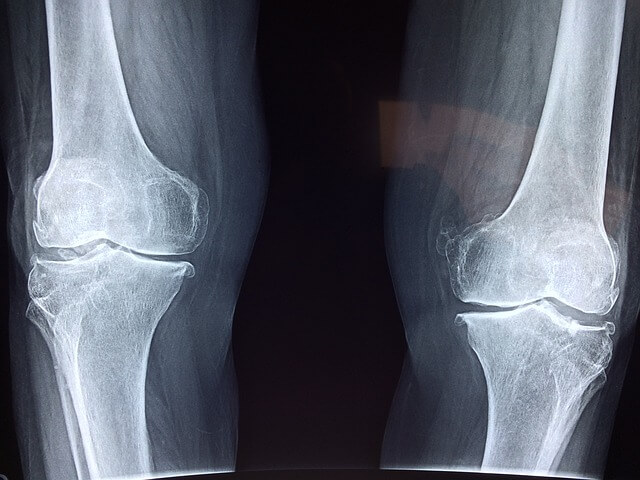

1. 관절 건강: MSM은 연골 형성 및 유지를 지원함으로써 관절 건강에 도움을 줍니다. 관절 통증과 염증을 완화하기 위해 그리고 쑤심과 붓기를 줄이기 위해 사용됩니다. 연구 결과 MSM이 동물 모델에서 관절염의 손상과 증상을 줄였다는 보고가 있습니다. 또한 인간의 경우 MSM을 복용하는 데 도움이 되는 것으로 나타났습니다.

5. 관절 통증: MSM은 관절 통증과 관련된 신경통증 및 염증을 완화하는데 효과적입니다. 관절 및 활동성을 개선하여 질병으로 인한 작업 부하와 통증을 줄이고 마디발증 치료에 유용하다고 알려져 있습니다.